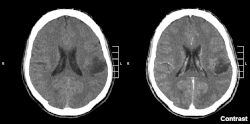

Her current research is an interventional clinical trial studying the treatment of young patients with recurrent or refractory low grade glioma, due for completion in 2020.[3][4] The group received the Jeremy Jass Prize for Excellence in Pathology for this work[5].

Glioma of the left parietal lobe. CT scan with contrast enhancement.